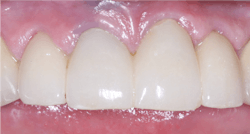

Although this category of restorations is decreasing in use due to implant placement, FPDs are occasionally needed. Clinicians Report Foundation has proven the viability of the original BruxZir in these situations (figure 4).